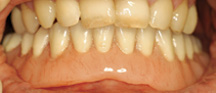

Missing a tooth ? An Implant can replace that missing tooth in no time. Modern dental implants are precision devices, the most common type is a titanium screw that is anchored into the jawbone where it serves as post for a custom-made tooth crown. Once the crown is in place, you may not be able to tell it apart from your natural teeth.

Missing teeth and loose dentures make too many people sit on the sidelines and let life pass them by. However, today’s modern treatment plans can replace everything from a single missing tooth to a completely missing arch. Ask your dentist or dental specialist about the different dental implant options that are available to you. Don’t let another day go by without taking this important first step to restoring your confidence and your smile!